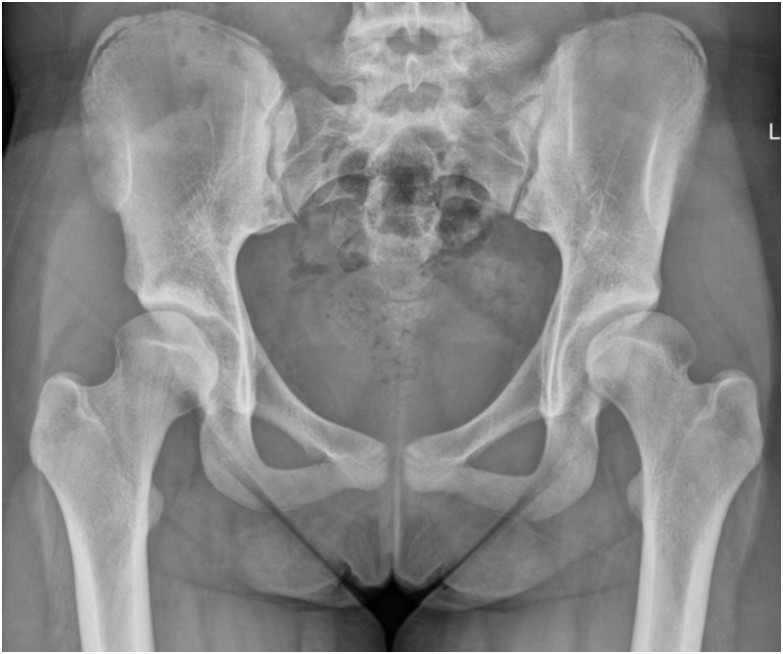

rzedstawiony radiogram wskazuje na złamanie okołoprotezowe typu: